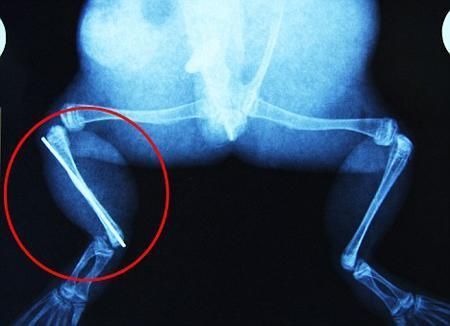

环球网4月2日报道 据《每日邮报》报道,上个月,南非大牛蛙布鲁莱的右小腿被邻居家的一只狗咬到,导致粉碎性骨折,现在经过2个小时的手术,它的断腿已经被接上,它也因此成为有史以来第一只通过外科手术用钢针接上断腿的青蛙。

布鲁莱的主人,居住在南非约翰内斯堡附近的62岁的安妮·米恩斯说:“我对这只青蛙如此关心,人们一定认为我疯了,但是我无法眼睁睁看着它那么痛苦。青蛙因其灵活的腿脚而著称,一想到布鲁莱的腿里要留下一个薄金属片,我就感到心痛。然而我知道,如果不进行手术,布鲁莱以后就没办法动弹了。因此我匆匆赶到兽医那里,央求他给这只可怜的青蛙动手术。这位兽医整天救助小猫小狗,他很难理解为什么我这么担心一只青蛙,但是最终他还是答应了给布鲁莱做手术。手术后是几个小时的焦急等待,我们希望它能快快苏醒过来。不过现在它的伤口已经愈合,又能在花园里跳来跳去了。X光照射显示,它会恢复的跟以前一样。”

野生生物专家安妮经常为学校写教材,她认为这是人类第一次通过手术给一只青蛙接断腿。在手术开始阶段,兽医把少量给狗用的麻醉药注入到这只青蛙体内,让它失去知觉。然后他在布鲁莱的断腿上切开一个小口,把一根小钢针植入腿里。最后兽医给它缝了9针,把切口缝合在一起。仅仅几周后,布鲁莱就能在安妮家附近活动了。这只青蛙大约已有25岁,主要以啮齿动物、蛇和其他青蛙为食。布鲁莱所属的牛蛙种群正在不断减小,目前只能在非洲南部的湿地里才能看到这种青蛙。